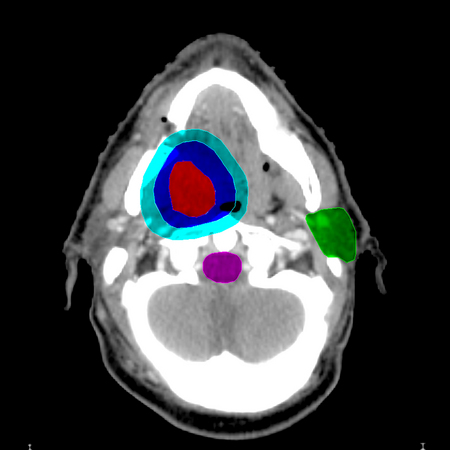

OAR, PRV

OAR (Organ at Risk) – “[OARs] are normal tissues whose radiation sensitivity may significantly influence treatment planning and/or prescribed dose.” Examples of OARs for radiotherapy of an oral cavity tumor can include the spinal cord, brainstem, and parotid glands.

PRV (Planning Risk Volume) – the OAR plus a margin, to compensate for movement and/or set-up errors of the OAR.